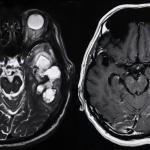

Екип от изследователи от САЩ и Япония разработиха нов тип ваксина, която преодолява защитната система на канцерогенните тумори и позволява на имунната система да ги унищожи. Те описват спецификите на ваксината и нейните ефекти при мишки и макаци резус в научното издание Nature.

До момента ваксината е тествана върху мишки и макаци резус и е безопасна. Изследователите отбелязват, че тя ще бъде още по-ефективна, ако бъде съчетана с радиотерапия. За в бъдеще те планират да я изпитат и върху хора.